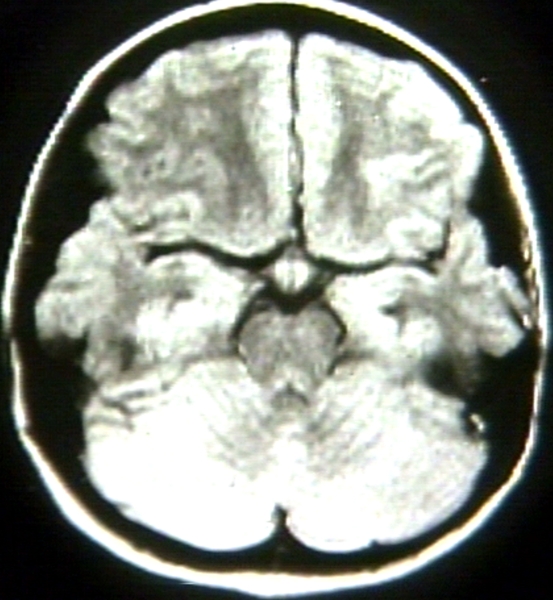

RADIOLOGY: NERVOUS: BRAIN: SUPRASELLAR MASS; T1 (MRI)